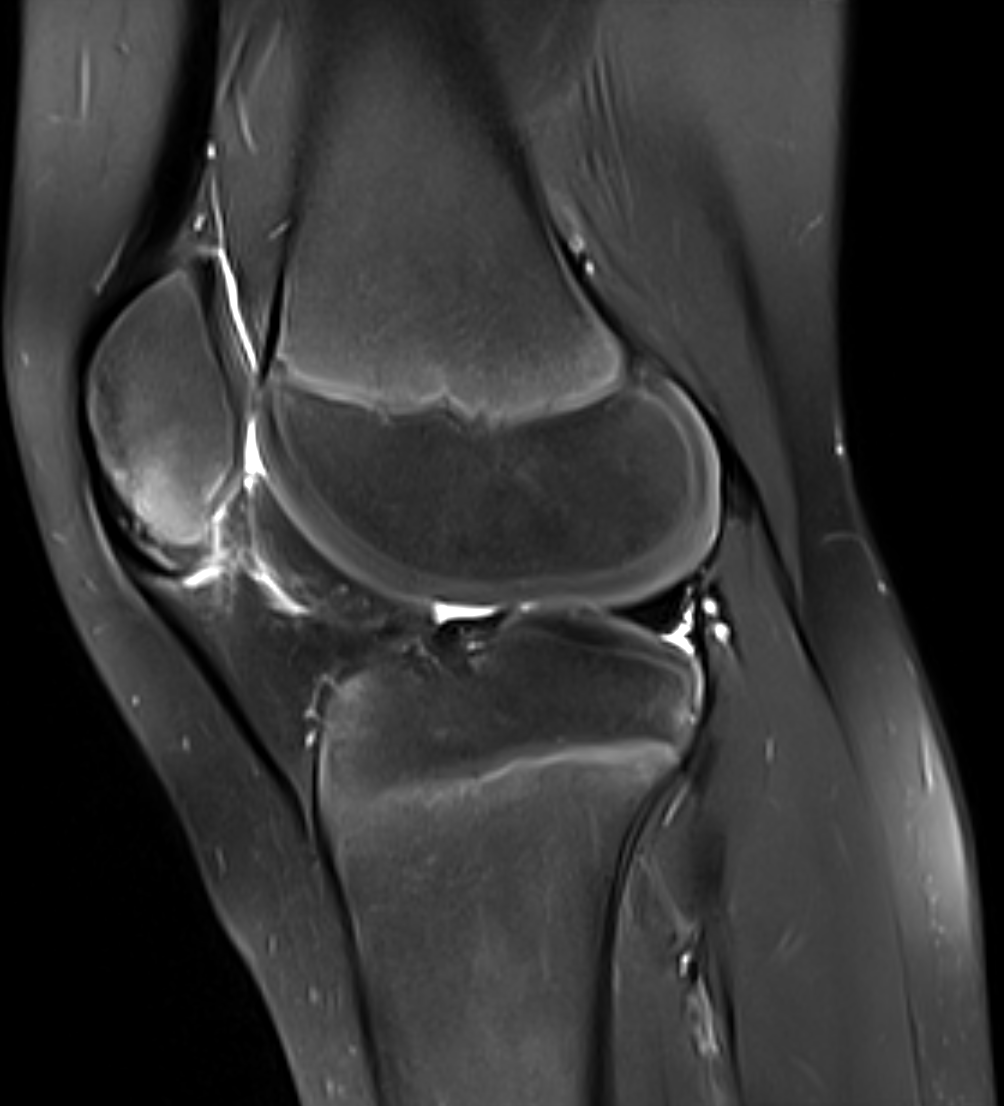

Inferior patellar apophyseal traction injury